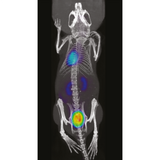

The β-CUBE is our high-performance preclinical PET imager.

Sub-millimeter image resolution is achieved through the combination of monolithic scintillators, the latest photon counting technology and GPU-based event positioning and iterative image reconstruction. The 5-ring configuration ensures best-in-class sensitivity over a field-of-view adequate for whole-body mouse and rat imaging at high count rate. In-house hardware allows for dynamic and gated studies. Intuitive and wireless acquisition software combined with our multimodal small animal bed allow for easy and modular multimodal imaging along with the γ-CUBE (SPECT) and X-CUBE (CT).